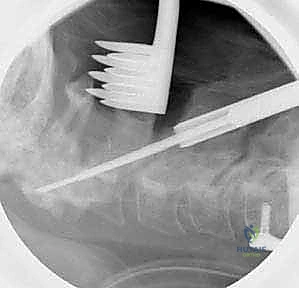

الخطوة 7: التصوير الشعاعي داخل العمليات

طوال الإجراء، وخاصة بعد تركيب المسامير والقضبان، يتم استخدام جهاز الأشعة السينية المحمول (C-arm